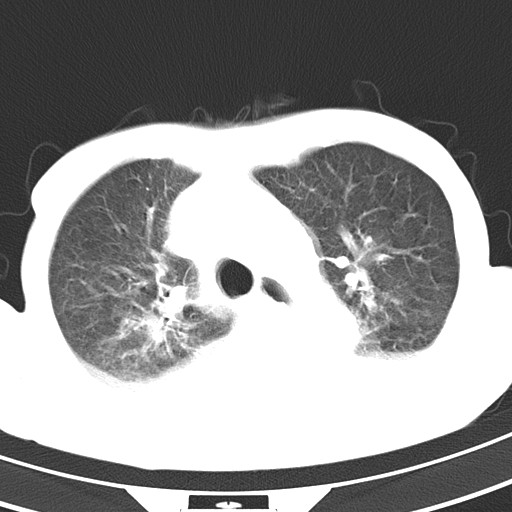

标题: CT21467:女,93岁,摔伤后检查。

女,93岁,摔伤后检查。

右肺炎症,心功能不全伴双侧胸腔积液,右下肺膨胀不全,食管裂孔疝,冠脉钙化,心包少量积液,左侧肋骨骨折,请上传骨窗.

双肺感染合并双侧胸腔积液、胸膜增厚粘连,骨性胸廓未见明确骨折征。

创伤性湿肺,双侧胸腔积液。可能有食管裂孔疝,进一步检查。骨折有无根据自己的机器及片子再仔细看吧。

右侧锁骨\\肩胛骨骨折、右侧湿肺,心功能不全伴双侧胸腔积液,右下肺膨胀不全,左膈破裂或食管裂孔疝,冠脉钙化,心包少量积液,请上传骨窗.

右肺炎症,心功能不全伴双侧胸腔积液,右下肺膨胀不全,食管裂孔疝,冠脉钙化,心包少量积液,左侧肋骨骨折,右肩甲骨粉碎性骨折。93岁,高寿哇!

右肺炎症,心功能不全伴双侧胸腔积液,右下肺膨胀不全,食管裂孔疝,冠脉钙化,心包少量积液,左侧肋骨骨折,右肩甲骨粉碎性骨折。